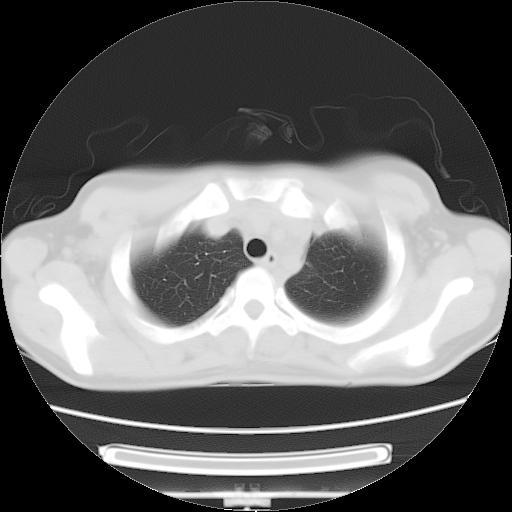

女,29岁,胸部不适,在外院胸片提示胸腔积液,到我院ct检查。

肺窗:

1、左侧包裹性积液伴叶间积液 2、右肺多发结节考虑增殖结节

左侧纵隔胸膜包裹性积液、左侧胸腔积液、胸膜肥厚粘莲,考虑结核性胸膜炎

左肺上叶不张,左侧胸水,叶间裂积液,纵隔淋巴结,脾脏钙化,考虑左肺上叶支气管内膜结核,结核性胸膜炎,脾结核

考虑:1.两肺tb;2.左侧胸膜炎、胸腔积液。

考虑两肺结核,左侧包裹性积液,叶间积液。

支持两肺继发性肺结核,左侧胸膜腔包裹性积液、胸膜肥厚,脾内多发钙化(结核钙化)。

右肺多发结节。左胸腔多发包裹性积液。